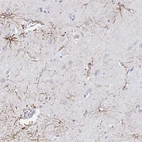

Immunohistochemistry analysis in human cerebral cortex and pancreas tissues using Anti-NR2E1 antibody. Corresponding NR2E1 RNA-seq data are presented for the same tissues.